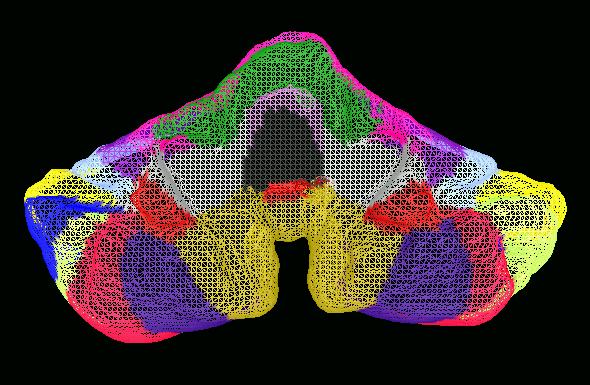

The surface from the region of interest is obtained by creating a

triangulated representation of the isolated surface, using a variant of the

marching cubes algorithm. One of the difficulties is that the resulting surface

must be topologically correct and have no defects. This means that the

surface must be equivalent to a sphere: it can have no holes or no bridges

(handles). Here is an example of the surface representing the

human cerebellum that was obtained. Various lobes and fissures have been

color-coded in the same manner as on the MRI slice.